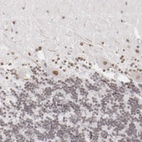

Immunohistochemical staining of human Fallopian tube shows moderate nuclear positivity in glandular cells.